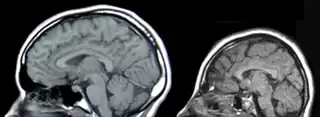

![]() Resonancia Magnética de la Cabeza, Izquierda: Normal, Derecha:Microcefalia. | ||